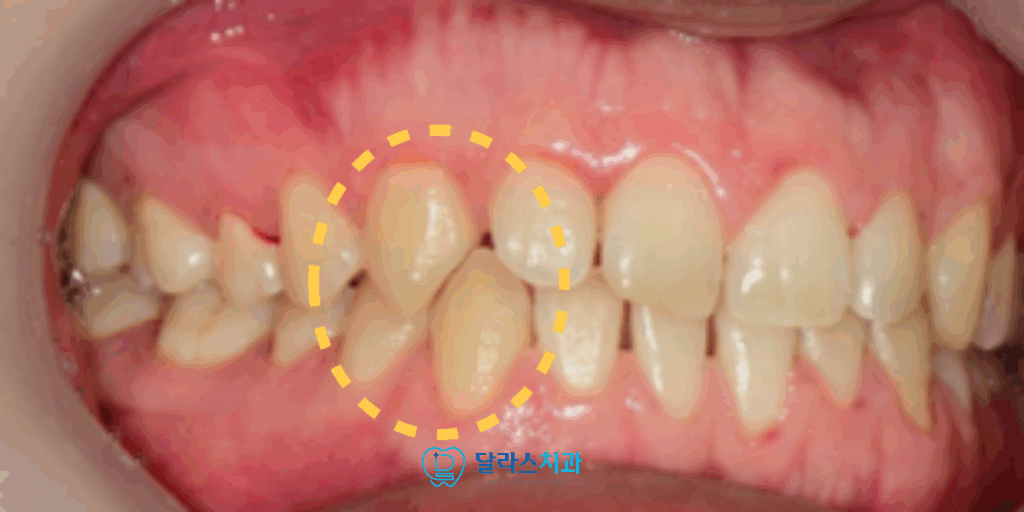

오른쪽 위의 두 번째 앞니를 보면 치아의 모양이 기형적인 것을 확인할 수 있습니다.

이 기형치로 인해서 교합관계가 방해를 받아서 정상적으로 물리지 않고 있었습니다.

또 한 가지의 문제점은 송곳니가 너무 깊게 맞닿아있는 딥바이트로 인해서

정상적인 “Canine guidance” 가 이루어지지 못하고 있었습니다.